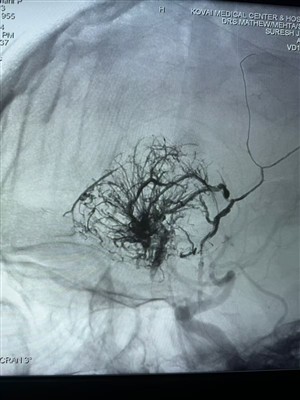

Prvi slučaj hipervaskularnog tumora prijavljen u IndijiDrago mi je što mogu podijeliti ovaj prvi slučaj hipervaskularnog tumora izveden u Indiji. Liječen je Lava Liquid Embolic Systemom tvrtke NeuroSafe Medical Co., Ltd.. Zahvaljujući dr. Mathewu Cheri...